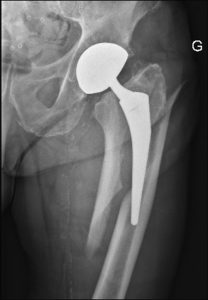

Femoral stem prosthesis is one of the main components of the total hip replacement (THR) which would be inserted through the proximal third femur bone to be articulated with the acetabular prosthesis. The function of the femoral stem is to establish the mechanical column for replacement of the femoral head. It acts as the load-bearing element against of bending and compressive stresses which is created at the articulation surface. The femoral stem prosthesis and femoral ball would form the overall femoral prosthesis to be assembled together and replaced through the femur bone to form the substitution structure for the worn cartilage tissue of the femur bone at the hip joint.

Femoral stem prosthesis is one of the main components of the total hip replacement (THR) which would be inserted through the proximal third femur bone to be articulated with the acetabular prosthesis.

Femoral stem is designed in different sections or portions as neck, metaphyseal, and diaphyseal.

The neck portion is dedicating the femoral neck of the femur bone, while the metaphyseal and diaphyseal portions are designed to be anatomically matched with the anatomy of the proximal third bone at the trochanter and diaphyseal sections of the femur bone at the proximal third.

The design of the femoral stem in frontal plane would be managed with extended width at the proximal portion and narrowed gradually to the distal portion to be replaceable through the intramedullary canal of the diaphysis bone.

The extended width portion would be at the trochanter zone.